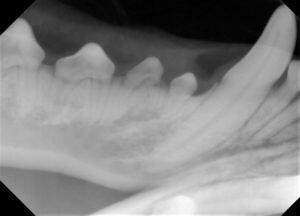

5.歯科レントゲンで歯と骨の状態を確認して

6.すべてのレントゲンを撮ってから、治療計画を立て